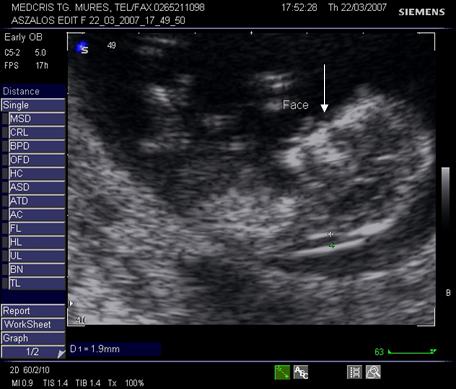

Fig. nr.23. Fata fetala la 11 sapt.